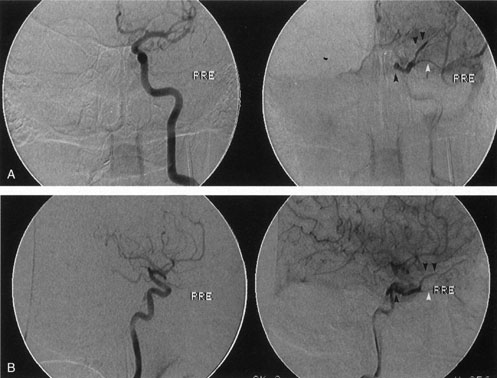

Fig. 17. Left internal carotid angiogram. The internal carotid artery within the cavernous sinus is seen in anteroposterior projection as a dark circle (A) and in lateral projection as an S-shaped structure (B). The fistula (black arrow) in this patient drained anteriorly into the superior ophthalmic vein (double arrow) and inferior ophthalmic vein (white arrow). In the absence of a history of trauma, the presumed etiology of the fistula in this patient was rupture of a preexisting intracavernous aneurysm.